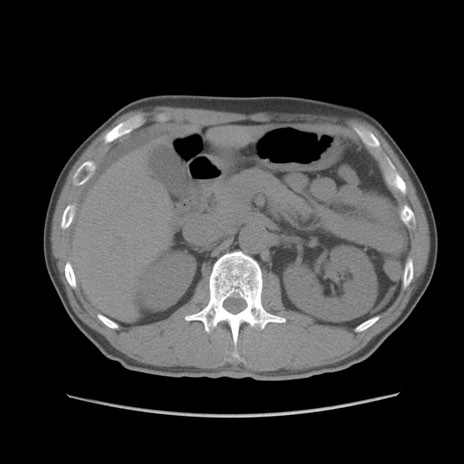

症例56 CT(横断像)

脂肪ウインドウ